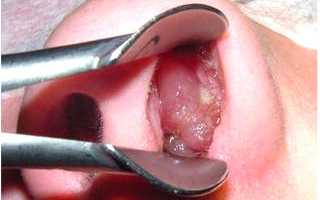

Эти проявления действительно напоминают грипп или ОРВИ. Спустя один-два дня симптомы исчезают, и на губах или слизистой носа возникает сильный зуд и жжение. Через несколько часов появляются маленькие пузырьки, наполненные прозрачной жидкостью.

Когда пузырьки лопаются, на их месте образуются болезненные язвы. Если не расчесывать их, они вскоре подсыхают и покрываются плотной корочкой. Эта корочка может оставаться до нескольких дней, а затем самостоятельно отпадает. Начинается период ремиссии, и вирус не проявляет себя до следующего обострения.